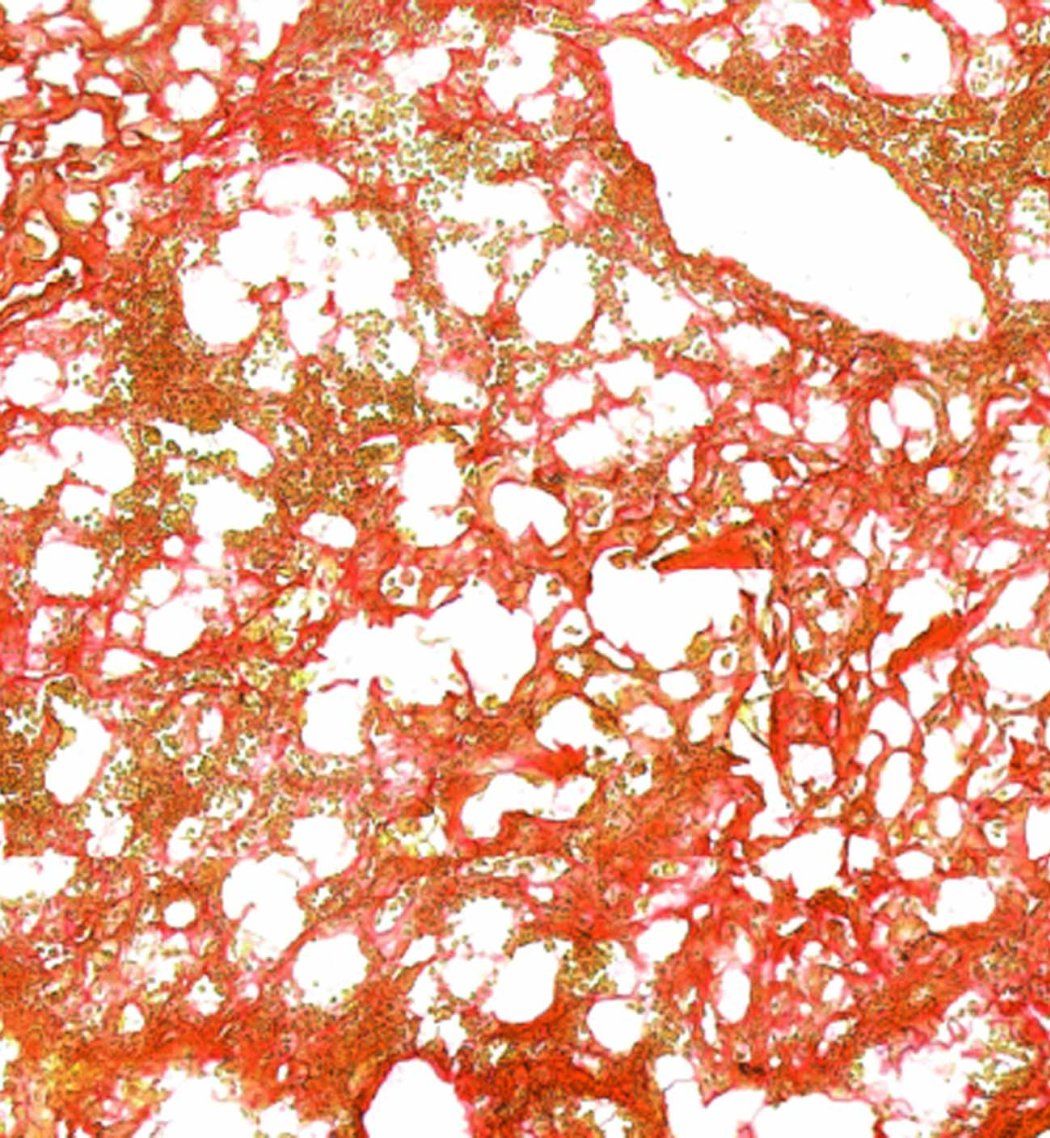

Area of mouse lung with established fibrosis.

A microscopic image showing the presence of harmful fibrosis in a lung.